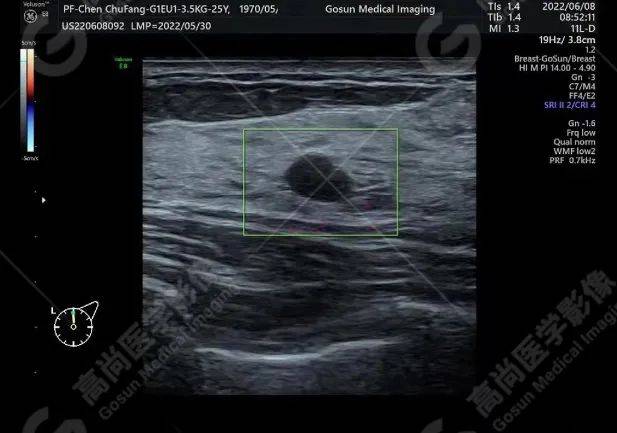

【高尚超声】乳腺纤维腺瘤_肿块_检查_乳房

图片尺寸617x433